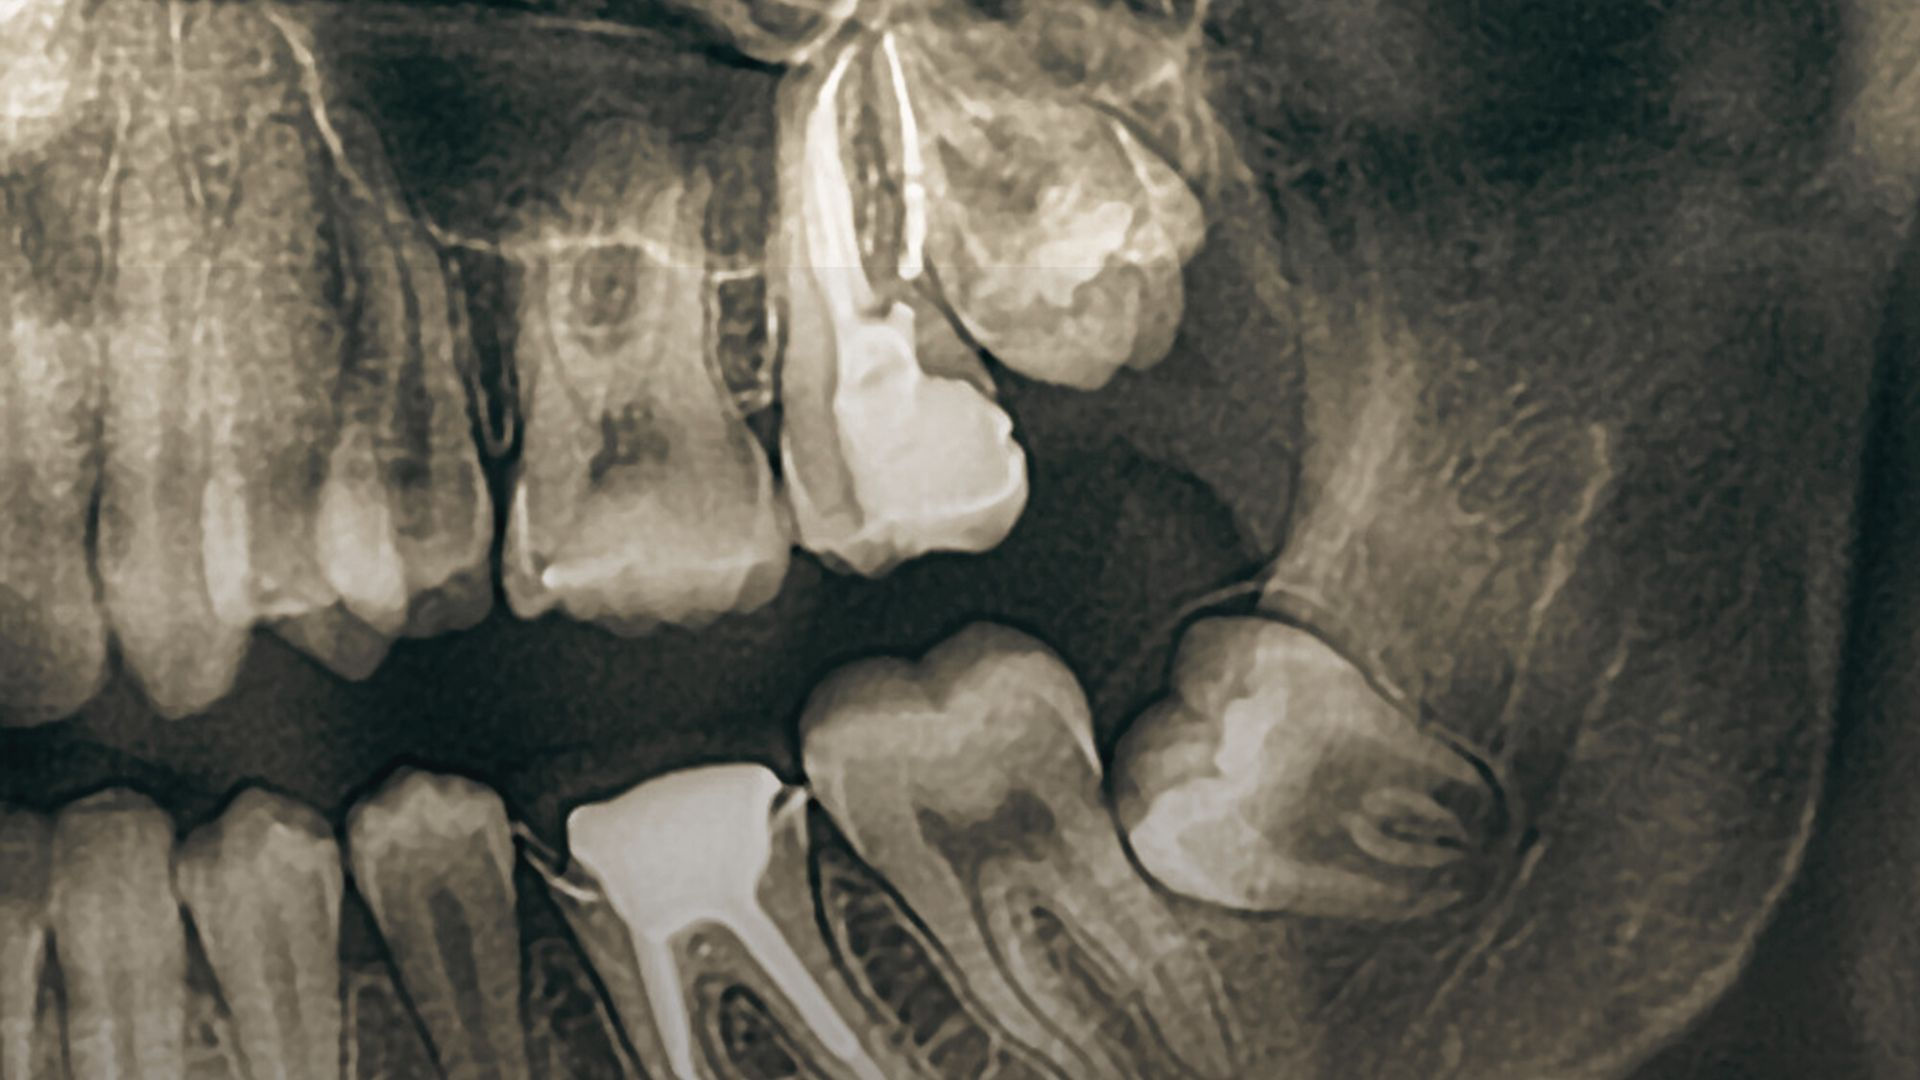

Dental Radiology

Prices from

$40

$100

$180

Periapical / Bitewing X-ray

OPG / Lateral Ceph

Cone Beam CT Scan (CBCT)